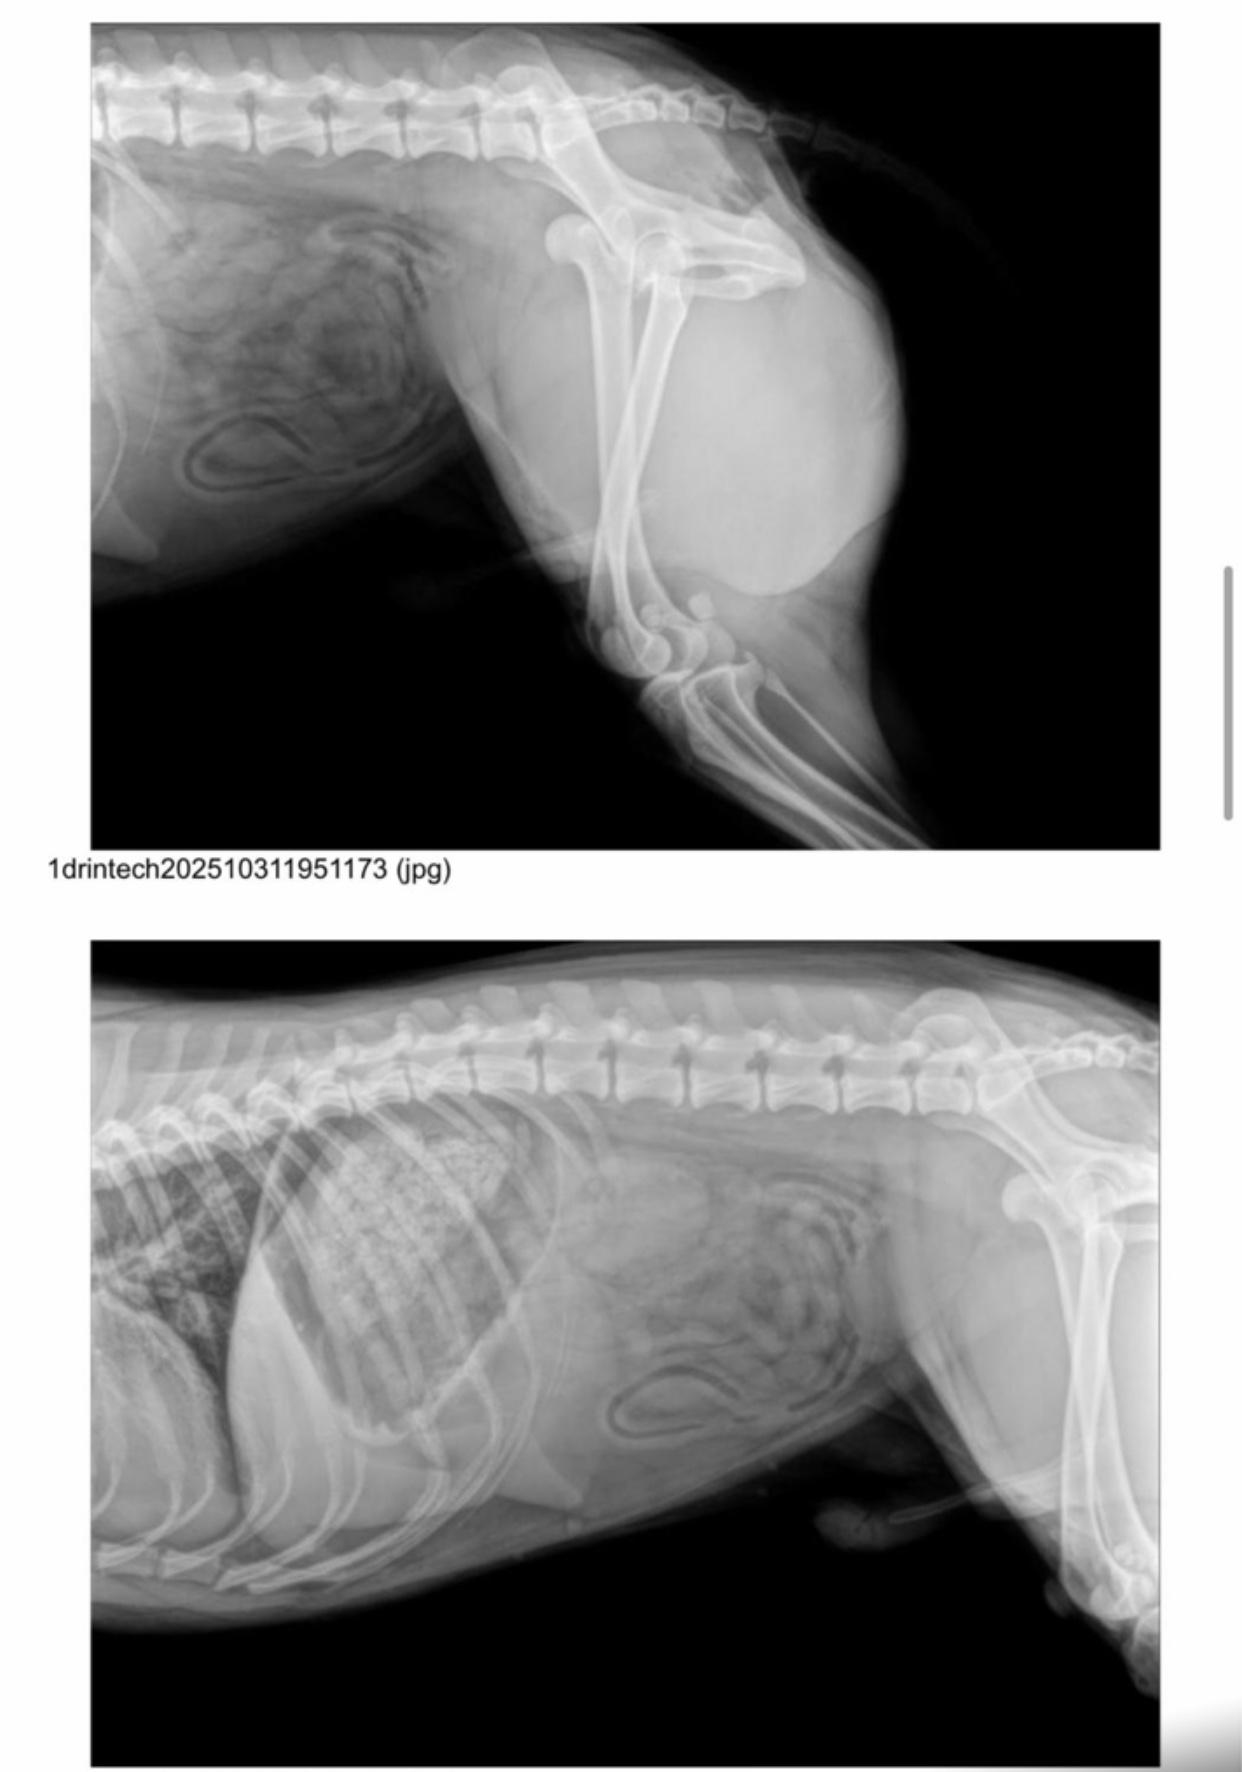

He’s a good boy who recently came to live with us after being hit by a car, which dislocated his hip. He’s currently recovering well from surgery. Son is very easy to handle and lets us treat him; he even licks your hands while you do it. He’s a trusting dog who readily accepts your requests. He walks well on a leash and is very attentive to anything you ask of him. He gets along well with other dogs, both male and female, large and small, and we’re sure he’ll start playing with them soon. Although he’s a young Podenco, he has a very calm energy and has rested without any problems after surgery. We believe he’s a good boy who deserves a family to play and go for walks with. Despite his hip injury, he can live a normal life, going on hikes and doing anything his new family wants him to do.